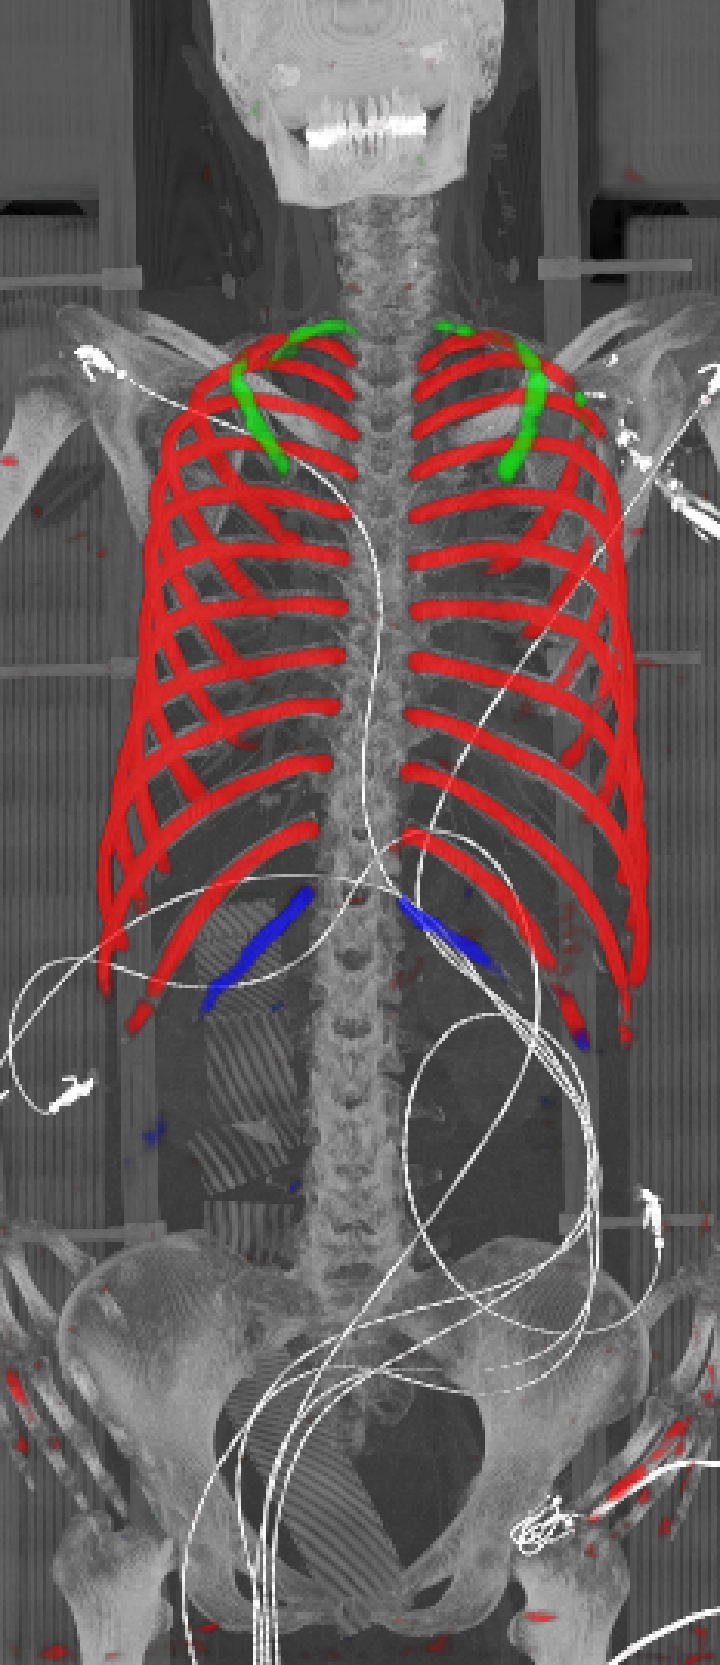

As can be seen from Table 2, we obtain overall good performance for the overall rib detection captured for example with an mean Dice of 0.84. Let us remark that for thin objects, such as the dilated rib centerlines, the Dice score constitutes a rather sensitive measure. The results indicate that detecting the first and twelfth rib pairs is more difficult for our network. While extraction of the first rib is more challenging due to, e.g., higher noise in the upper thorax or other bony structures in close vicinity (clavicle, shoulder blades, vertebrae), the twelfth rib can be extremely short and is easily confused by the neighboring ribs. For further illustration, Figure 4 shows the results on selected representative cases. Generally, the ribs are well detected without major false responses in other structures - despite all the different challenges present in the data. The color coding highlighting of the multi-label detection reveals that first and twelfth are mostly correctly detected. In few cases the network wrongly generated strong responses of the classes first rib or last rib for voxels belonging to the second or eleventh rib pair.

Refer to caption

Figure 4: Maximum intensity projections (MIP) of selected CT volumes overlaid with the multi-label output of the neural network (green: first rib; red: intermediate rib; blue: twelfth rib). The selected case above display common difficulties which are inherent in the data set, such as pads (a) or cables (b), internal devices such as pacemakers (c), stents (d), spinal (e) and femural/humeral implants (f), injected contrast agents (g), patient shape variations such as scoliosis (h), limited field of views (FOVs), i.e. partly missing first (i) or twelfth rib (j).